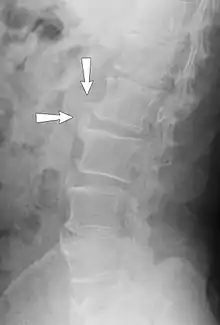

| Small marginal osteophytes (arrows) of the processus anconeus of the ulna can be seen in this gross pathological specimen of a sow. | |

Osteophytes form naturally on the back of the spine as a person ages and are a clinical sign of degeneration in the spine. In this case, the osteophytes are commonly not the source of back pains, but instead are a sign of an underlying problem. However, osteophytes on the spine can impinge on nerves that leave the spine for other parts of the body. This impingement can cause pain in both upper and lower limbs and a numbness or tingling sensations in the hands and feet because the nerves are supplying sensation to their dermatomes.[6]